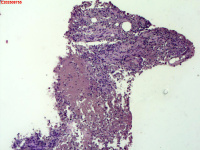

- 右侧胸壁穿刺组织活检

| 性别 | 女 | 年龄 | 81岁 | 临床诊断 | 胸锁关节结核? |

| 一般病史 | 胸部CT示:右肺下叶小结节,建议3-6个月复查,必要时胸外科会诊。左肺上叶多发小斑点、结节影,结核可能。右肺上叶多发点状影。双肺间质性改变。纵隔淋巴结肿大、钙化。右侧胸锁关节见骨质破坏,周围见软组织肿胀。 | ||||

| 标本名称 | 右侧胸壁穿刺组织活检 | ||||

| 大体所见 | B超:体表包块彩超示右侧胸壁混合回声包块,右侧胸壁低回声区,CDFI示:其内未见明显血流信号。 | ||||